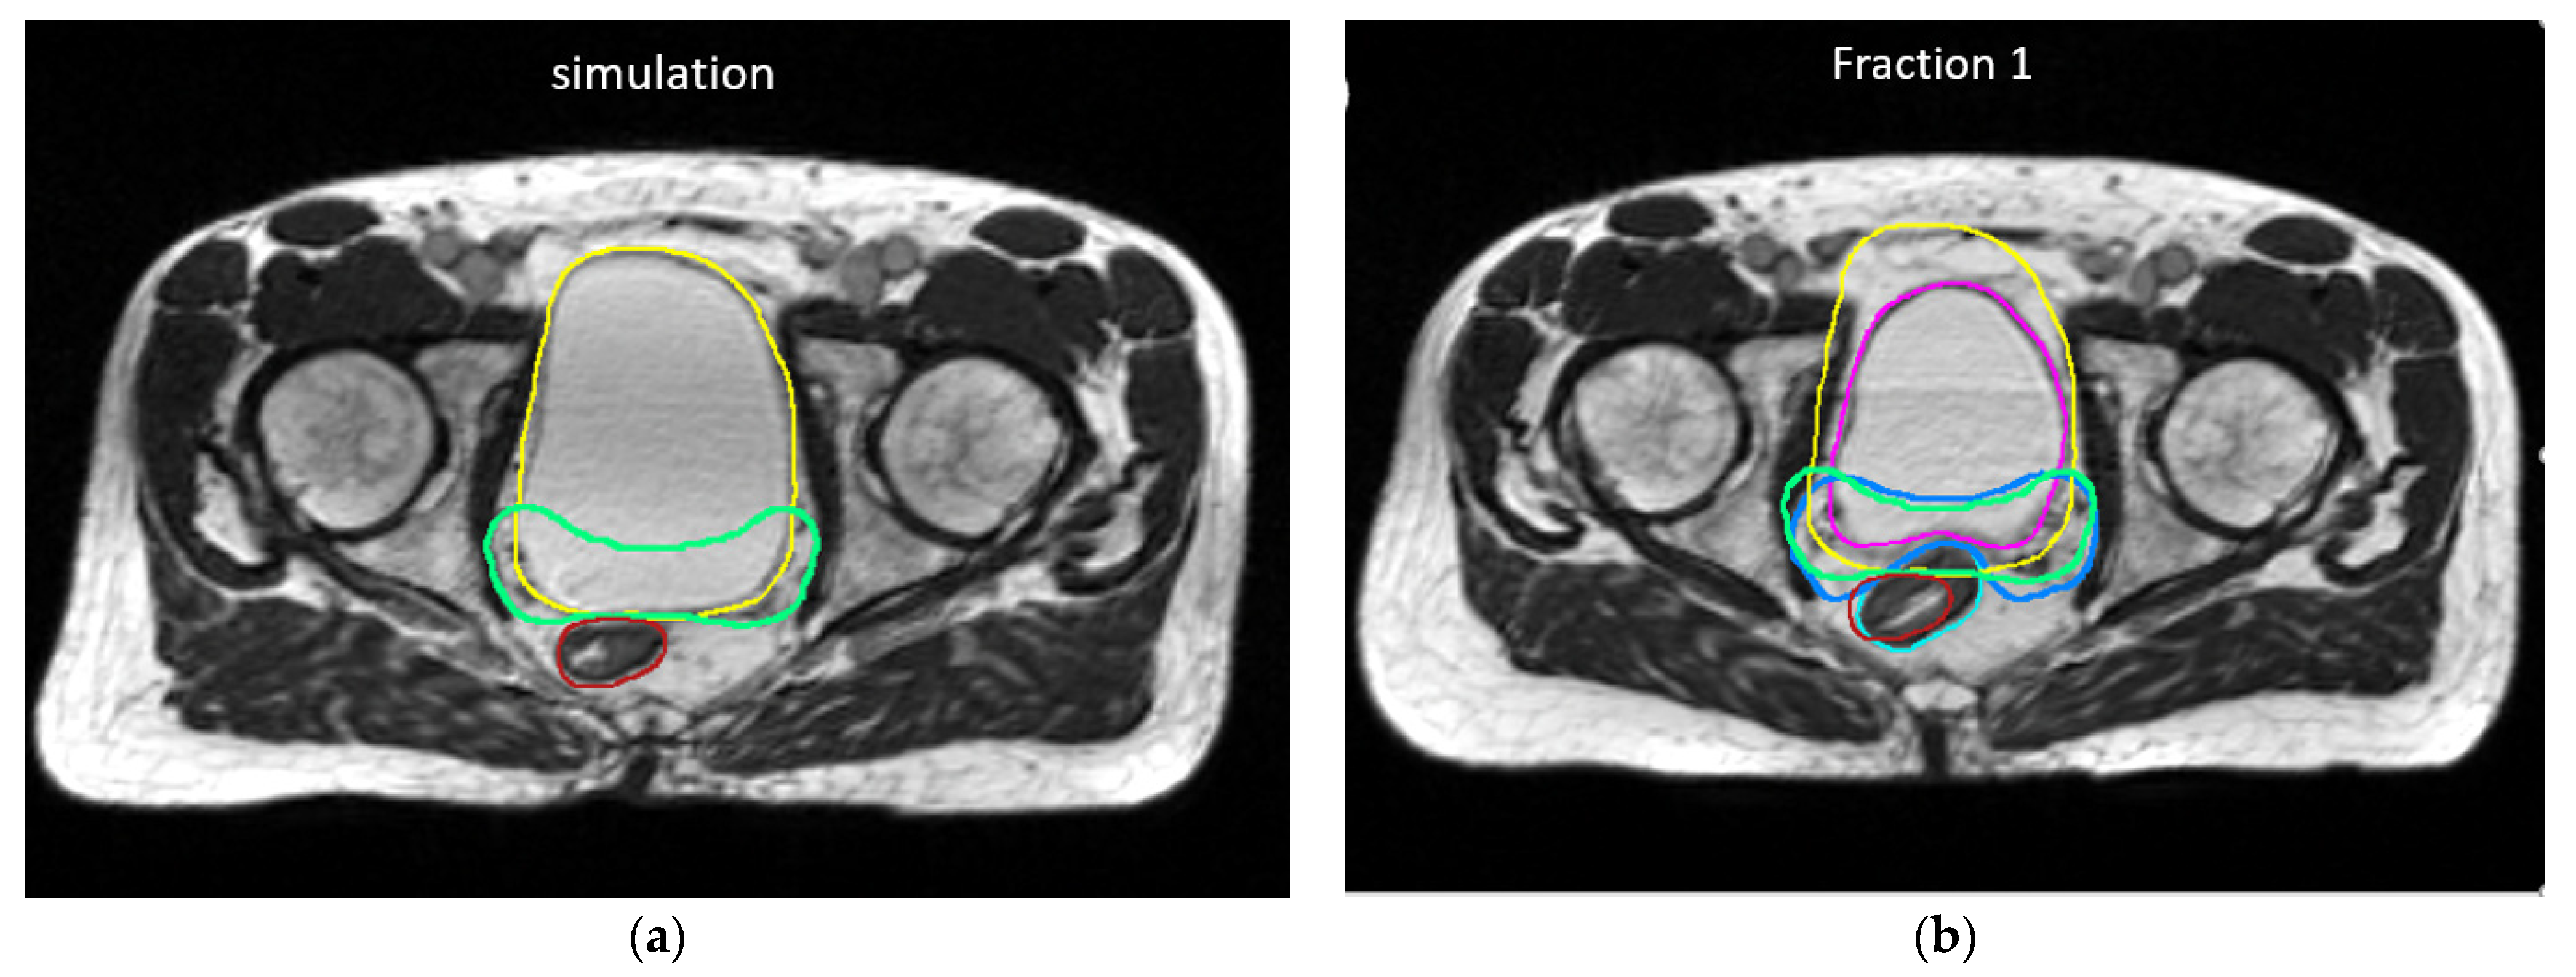

2. Materials and Methods

3. Results